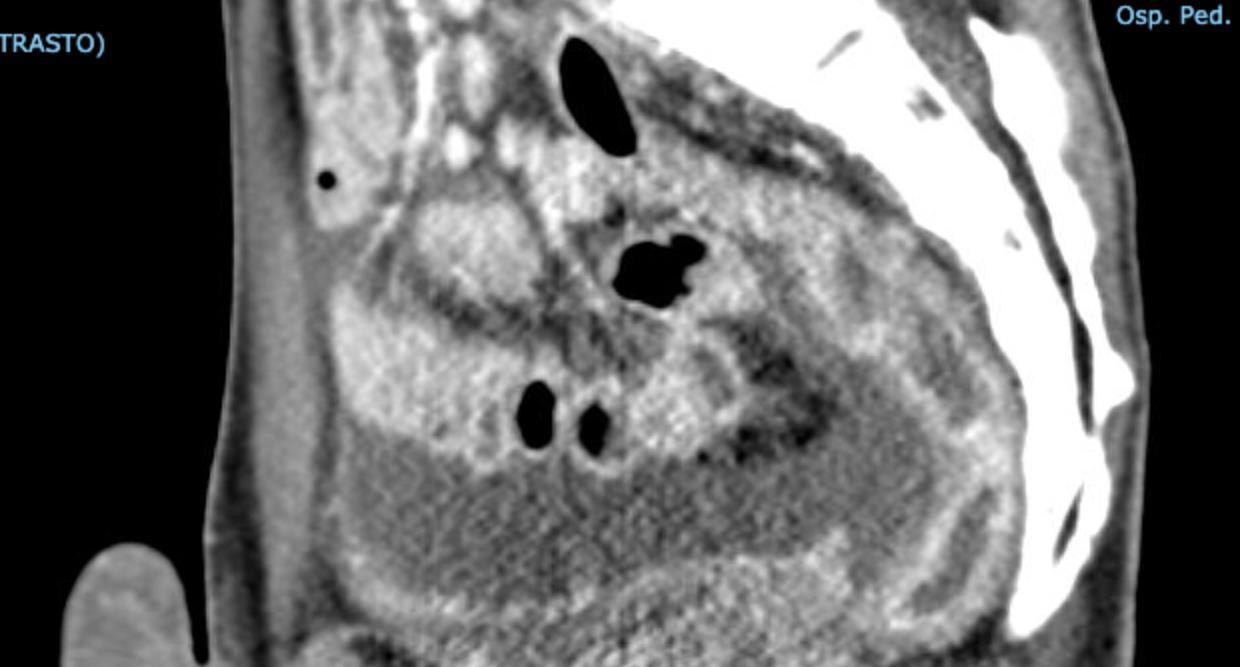

Pediatric COVID-19: MIS-C

Thoracic abnormalities

Abdominal abnormalities

Solid viscera abnormalities

Hepatomegaly

Splenomegaly

Hollow viscera abnormalities

Gallbladder wall thickening

Bowel wall thickening

Bowel dilation

Gastric distention

Urinary bladder thickening

Peritoneal abnormalities

Small ascites

Mesenteric abnormalities

Mesenteric lymphadenopathy

• Gastrointestinal (GI) symptoms (abdominal pain, diarrhoea and vomiting) are prevalent in MIS-C

• Abdominal pain in 62%

• Up to 90% any GI symptom

• Anumber of studies have described abdominal imaging findings including ascites, bowel wall thickening and mesenteric lymphadenopathy